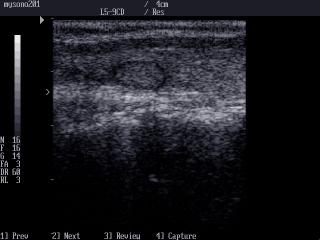

MySono-201. Thyroid nodule, B-mode.